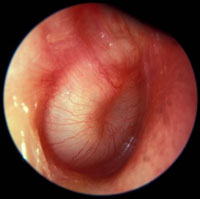

Injected Tympanic Membrane

Pink/red tympanic membrane

Often seen with fever, eustachian tube obstruction or viral URTI

Tympanic membrane is transparent (no effusion)

The handle of the malleus is visible and more horizontal